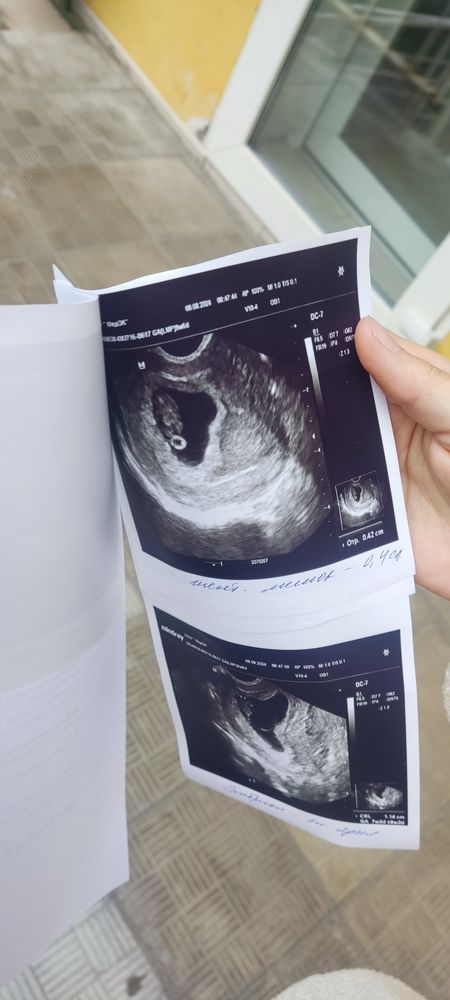

Подскажите про УЗИ

Все норм в узи, тонус отдыхать больше ❤️

Нормальное УЗИ ,тонус бывает у многих на таком сроке.Побольше отдыхайте и не поднимайте тяжести.